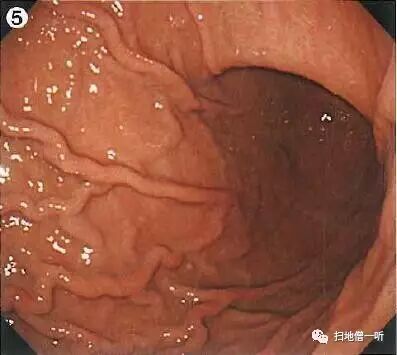

A:胃癌在图4及图5。HP未感染胃癌。

背景粘膜RAC阳性,提示HP未感染。穹隆部后壁可见一小片褪色粘膜,边界清晰,表面光滑,腺管扩张,伴随有蛇形血管。

靛胭脂染色后表面光滑,未见凸凹变化

NBI观察周围粘膜呈褐色改变,边界不甚清晰。

HE染色低倍镜观察红色为病变区域,周围区域为胃底腺区域

HE染色中倍镜观察病变区域粘膜中-深层可见轻度大小不等存在分枝的腺管密集增生

HE染色高倍镜观察可见细胞核类圆形排列于基底侧,胞浆淡嗜碱性,形态类似主细胞。考虑为粘膜内胃底腺型胃癌(主细胞优位型)。免疫组化染色:pepsinogen-I\muc6广泛阳性,H+/K+ATP极少阳性。

最终病理诊断:

穹隆部后壁,O-IIb,6mm,胃底腺型胃癌,T1a (M),UL(-)